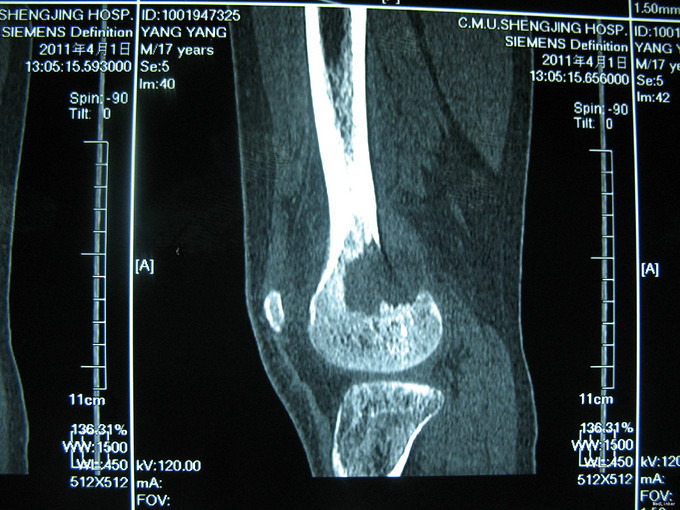

右膝上疼痛2个月肿胀一周 患者2个月前无明显诱因出现右膝上疼痛,逐渐加重,一周前活动后加重明显并开始出现肿胀,右膝关节活动受限,于当地医院行CT及MRI检查考虑为恶性肿瘤,遂来我院治疗。

入院后完善相关检查,诊断为股骨恶性肿瘤,考虑为骨肉瘤。切取部分肿物病理活检。病理明确诊断股骨骨肉瘤后,给予新辅助化疗。化疗效果明显,手术行瘤段切除人工假体置换术。